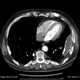

Loculated pleural effusion

Pleural empyema is a collection of pus in the pleural cavity caused by microorganisms, usually bacteria. Often it happens in the context of a pneumonia, injury, or chest surgery. [Source: Wikipedia ]